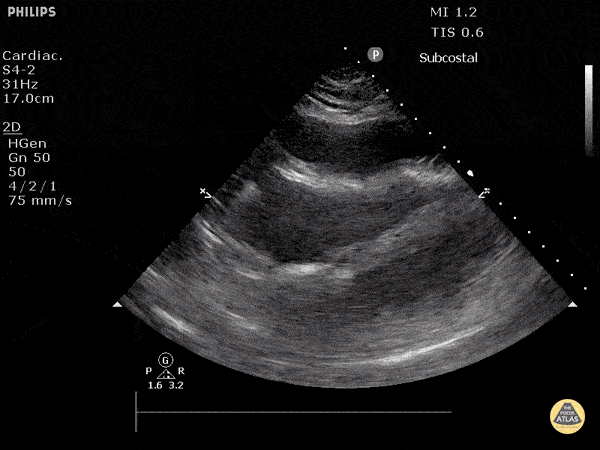

Subcostal view demonstrating signs of cardiac tamponade including right ventricular collapse during diastole. Justin Bowra MBBS, FACEM, CCPU Emergency Physician, RNSH et al. (Dr. Orr)